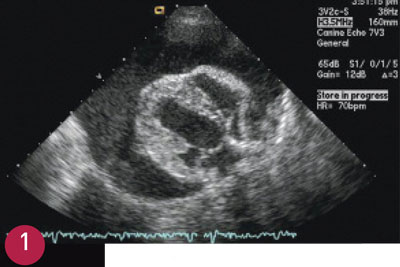

Plasma NT-proBNP concentrations are elevated in dogs and cats with congestive heart failure and those with asymptomatic heart disease (Figure 2). Several studies have shown plasma BNP or NT-proBNP to be sensitive and specific for the diagnosis of heart failure in dogs and cats presenting with cough or dyspnea (Table 1).9–13

FIGURE 2

Lateral thoracic radio­graph from a 10-year-old castrated male domestic shorthair cat with vague clinical signs of lethargy and loss of appetite of 1 day’s duration. No murmur or gallop was noted. The only physical examination abnormality was an elevated respiratory rate (60 breaths/min). Thoracic radiographs were suspicious for congestive heart failure, but the NT-proBNP level (1126 pmol/L) added confidence to the diagnosis.